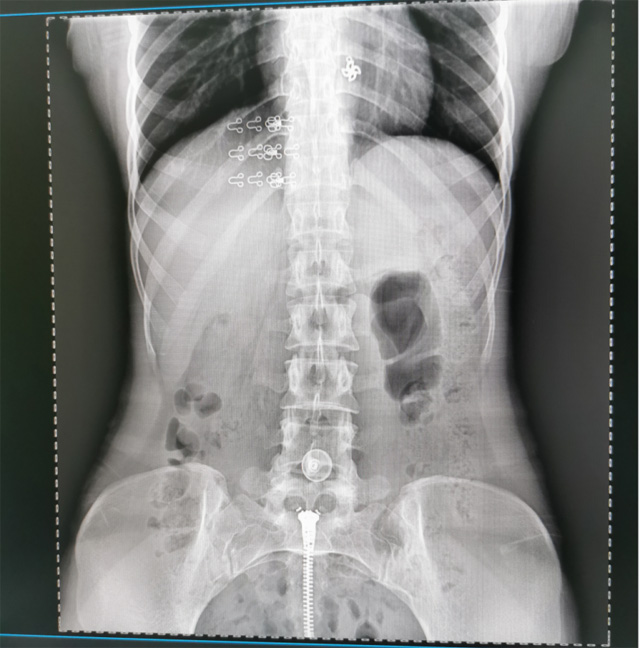

提高醫(yī)院的影像科的醫(yī)療服務(wù)水平,滿足滿足人民群眾不斷增長的醫(yī)療需求,促進醫(yī)療技術(shù)快速發(fā)展。醫(yī)院都引進懸吊DR拍片設(shè)備新一代數(shù)字化X線攝影系統(tǒng)。標志著醫(yī)院的診療水平又上升一個新的臺階。懸吊DR滿足人體頭部、胸部、腹部、腰椎、四肢等部位的數(shù)字攝影檢查,可以檢查呼吸系統(tǒng)疾病,心臟系統(tǒng)的疾病、骨關(guān)節(jié)系統(tǒng)的疾病,子宮輸卵管造影、胃腸道造影,.有職業(yè)病體檢篩查塵肺病功能。通過DR數(shù)字化攝影,分段連續(xù)、重疊采集數(shù)字化圖像,利用軟件對圖像進行拼接的方式來獲得全脊柱、全上肢或全下肢的圖像。新設(shè)備的圖像更清晰,臨床拍攝避免患者再次搬運和移動產(chǎn)生的痛苦,是創(chuàng)傷骨折患者的福音。輻射減少受照劑量50%,后處理能力強、圖像質(zhì)量高。有效降低操作難度,縮短工作流程,尤其適合大批量體檢。

具有射線劑量小、圖像清晰度高、誤差小等特點,懸吊DR已廣泛應(yīng)用于各級醫(yī)療機構(gòu)的體檢中心,越來越受到臨床醫(yī)生的肯定和患者的青睞。為臨床診斷工作提供更加直觀有效的技術(shù)支持,大大提高了患者就醫(yī)效率從而為患者提供更加優(yōu)質(zhì)的醫(yī)療服務(wù)。提高了其成像質(zhì)量和臨床應(yīng)用價值,并極大減少了受照輻射劑量。有效滿足了各種常見疾病的臨床診斷和治療需求。以醫(yī)療質(zhì)量為根本,以優(yōu)質(zhì)服務(wù)為導向,竭誠為人民群眾的健康保駕護航。